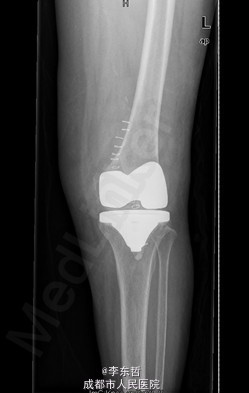

患者女,74岁,因“双膝疼痛20年,加重伴行走困难8年”入院。患者诉20年前开始出现双膝关节疼痛,负重行走、下楼时疼痛加重,休息后可缓解,尚可下蹲。自行购买止痛药口服,关节腔内注射玻璃酸钠、理疗等处理,疼痛时有缓解。但症状反复发作。8年前疼痛加重且行走困难,扶拐行走仅能坚持约10余米,上下楼梯艰难,下蹲不能,以左侧为重。遂来院就诊。

查体:跛行步态,双膝关节屈曲内翻畸形,双膝内侧间隙压痛,双膝髌股关节间隙压痛,左膝伸-20°,屈110°内翻10°。右膝伸-20°,屈110°内翻10°,双膝屈伸活动时髌骨下摩擦感(+)。 辅助检查:X片示双侧髌股关节内侧间室变窄,关节边缘骨赘增生,软骨下骨硬化。

入院诊断:1、左膝骨关节炎伴屈曲内翻畸形; 2、右膝骨关节炎伴屈曲内翻畸形; 诊疗计划:1、向患者及家属交待病情及注意事项。2、向上级医生汇报患者病情。3、完善相关术前检查;4、择期手术。